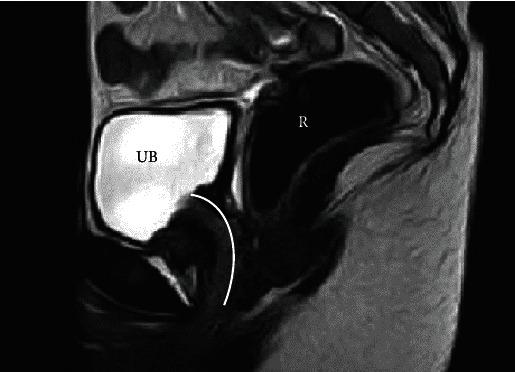

Mayer-Rokitansky-Küster-Hauser (MRKH) syndrome is a female congenital disorder characterized by an underdeveloped or absent vagina and uterus. The first-line treatment to create a neovagina is patient-performed vaginal dilatation. We report here the rare case of an MRKH patient who presented with urethral dilatation and was successfully treated with Davydov vaginoplasty. Seventeen-year-old patient with known single kidney was consulted by a gynaecologist, and a diagnosis of MRKH syndrome was established. As the patient had urethral dilatation-resulting from repetitive intraurethral intercourse-neovaginal creation by means of self-performed vaginal dilatation was precluded. Rather, the Davydov vaginoplasty was successfully performed; there were no postoperative complications, and the patient was fully continent postsurgery. MRKH patients and healthcare providers should be educated on the damaging consequences of intraurethral intercourse. More cases need to be reported to establish the best treatment options for a normal sexual life.

梅耶-罗基坦斯基-库斯特-豪泽(MRKH)综合征是一种女性先天性疾病,其特征为阴道和子宫发育不全或缺失。创建新阴道的一线治疗方法是患者自行进行阴道扩张。我们在此报告一例罕见的MRKH患者,该患者出现尿道扩张,并通过达维多夫阴道成形术成功治愈。一名17岁已知单肾的患者由妇科医生会诊,确诊为MRKH综合征。由于该患者因反复尿道内性交导致尿道扩张,因此无法通过自行进行阴道扩张来创建新阴道。相反,成功实施了达维多夫阴道成形术;术后无并发症,患者术后完全控尿。应向MRKH患者和医疗服务提供者宣传尿道内性交的有害后果。需要报告更多病例,以确定实现正常性生活的最佳治疗方案。